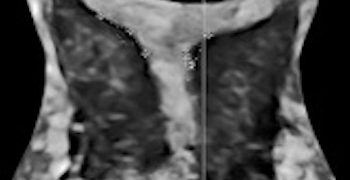

Anche a Dicembre un nuovo Journal Club relativo ad un nuovo segno ecografico in caso di Placenta Accreta Spectrum. Grazie a Gabriele Saccone! Buona Lettura! [pdf-embedder url="https://www.sieog.it/wp-content/uploads/2021/12/Journal-club-dicembre-2021.pdf" title="Journal club -...